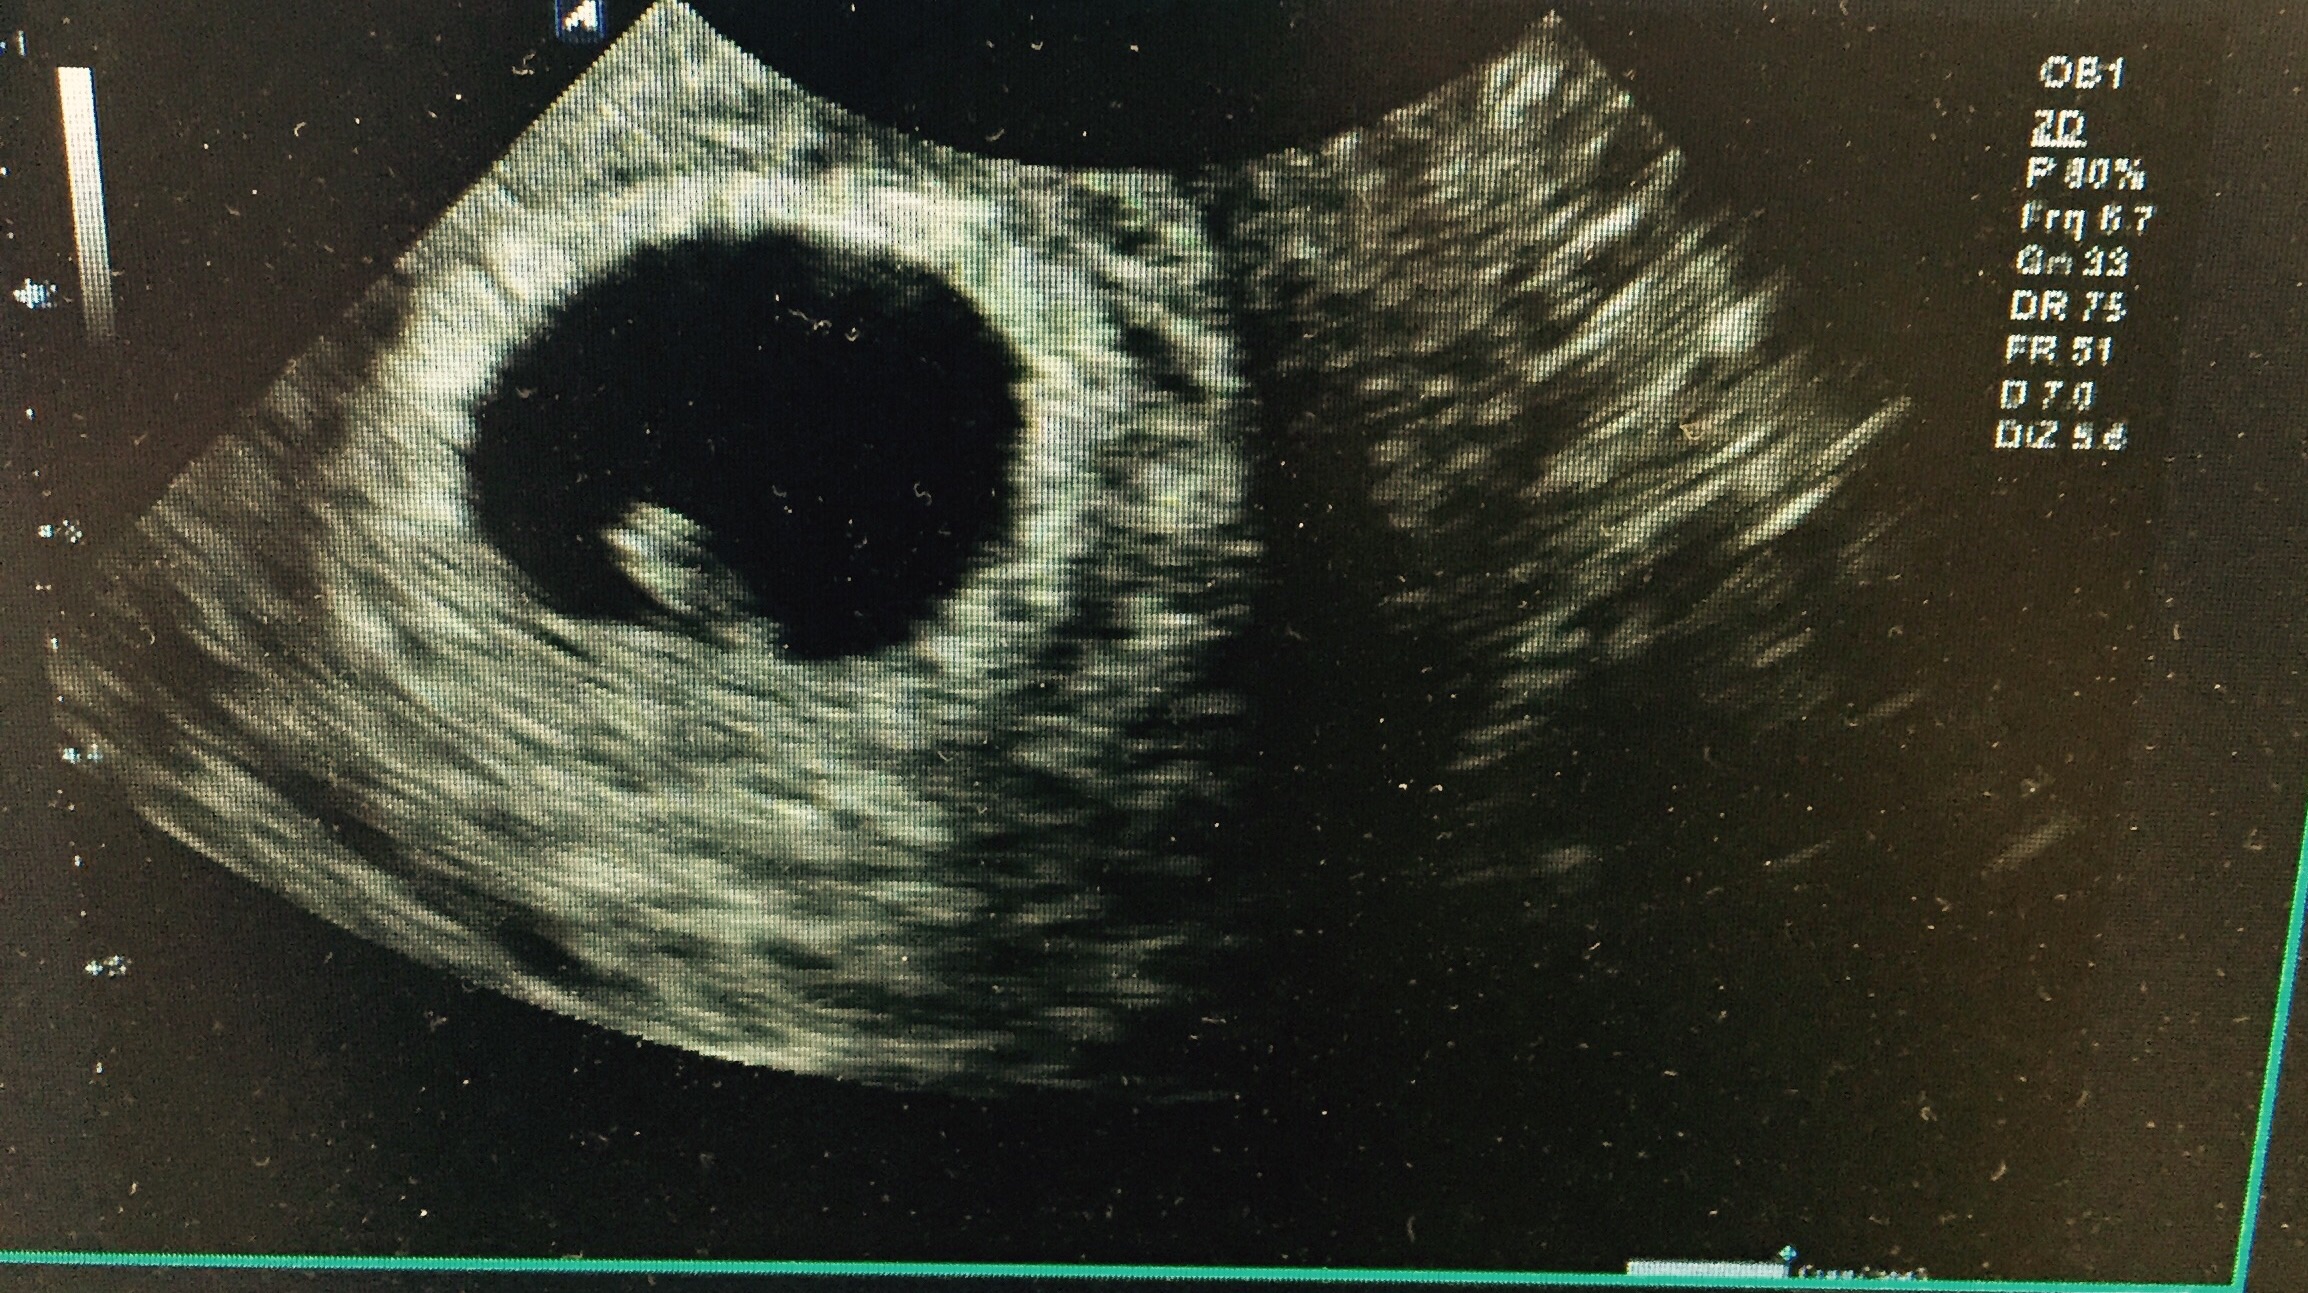

Twins!!!!!! I had two ultrasounds, one week apart.

I'm having twins too!! How far along are you?